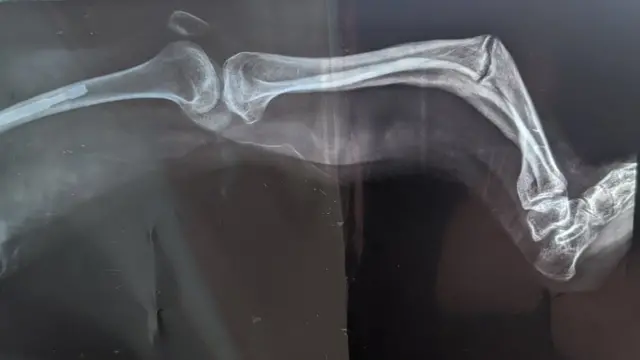

Madaktari walimpata na ugonjwa unaofahamika kama osteogenesis imperfecta, maarufu "brittle bone ".

Huu ni ugonjwa unaosababisha mifupa ya muathirika kuvunjika kwa urahisi sana, kwa kawaida bila majeraha ya aina yoyote, kama vile kuanguka.

Osteogenesis imperfecta ni ugonjwa unaosababishwa na kasoro katika jeni zinazohusika na utengenezaji wa aina ya kwanza ya collagen, ambayo husababisha mabadiliko hasa katika uundaji wa mifupa, tishu ngumu inayotengeneza meno, sehemu nyeupe ya macho na mishipa.

Ugonjwa wa "Mfupa wa Kioo" unaweza kugawanywa katika viwango vinne, mbaya zaidi ni aina ya 2, ambayo mtoto anaweza kujeruhiwa hata ndani ya tumbo la mama.

Kuvunjika kwa kawaida kunaweza kutokea baada ya kile kinachochukuliwa kuwa kiwewe kidogo na kunaweza kusababisha usumbufu mdogo. Hata hivyo, maumivu ya muda mrefu yanaweza kutokea kutokana na upungufu wa mifupa, ambayo ni sehemu ya mifupa iliyovunjika.